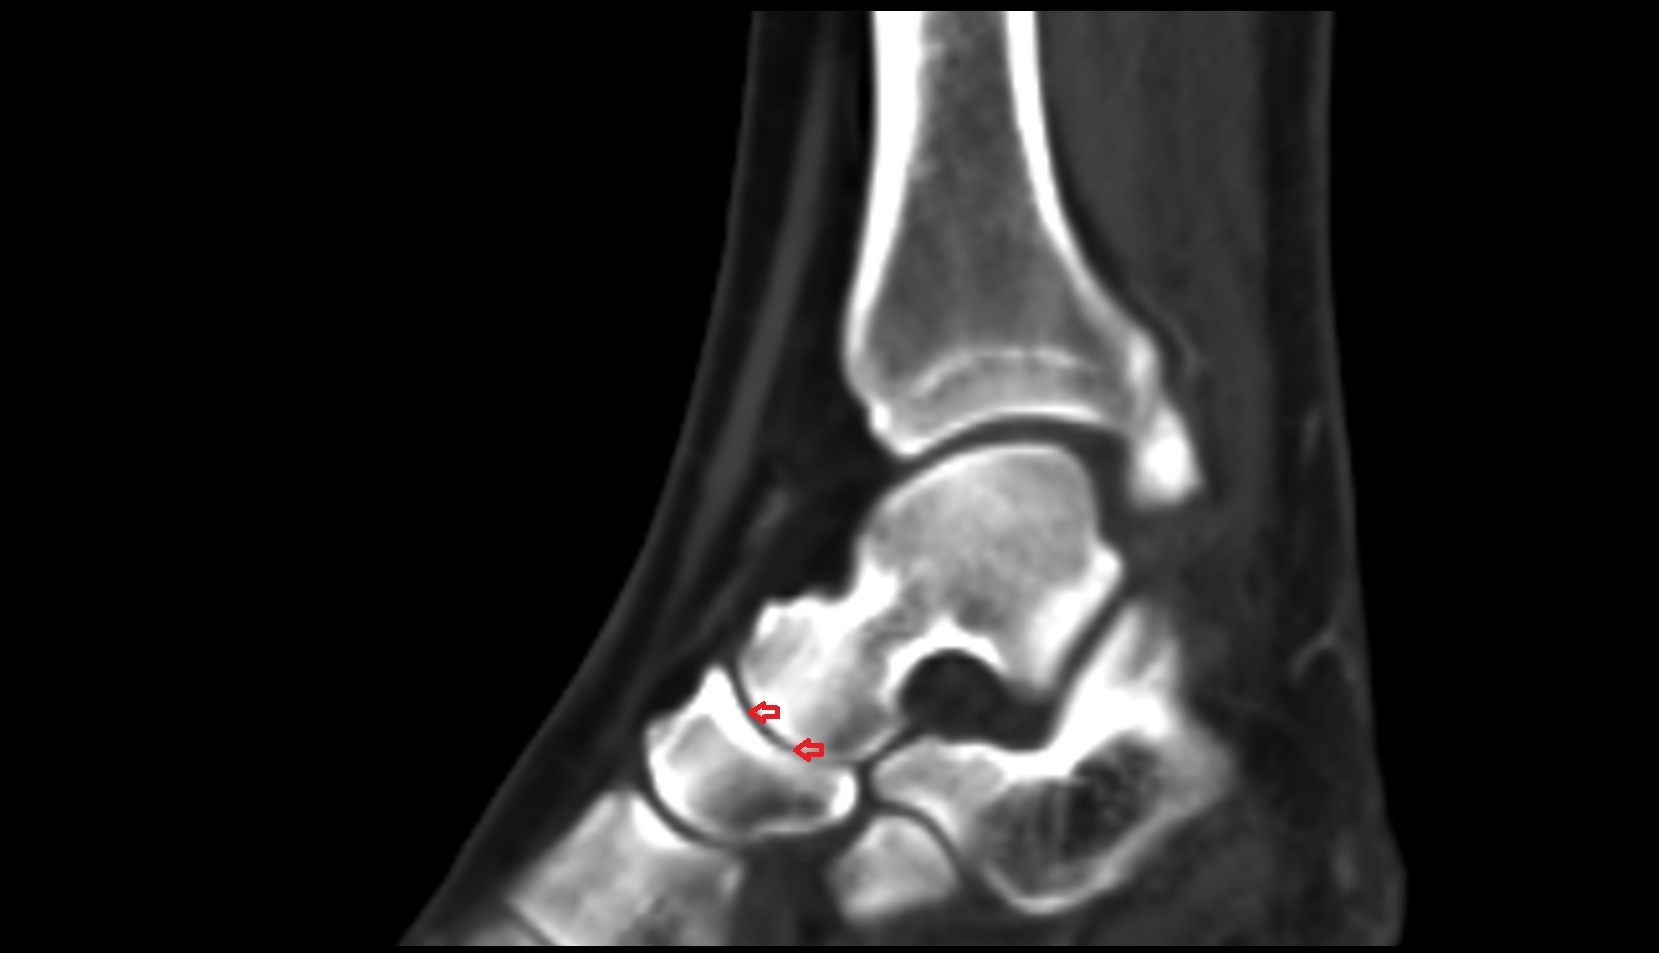

- Talus

- Head of talus

- Body of talus

- Neck of talus

- Calcaneus

- Sustentaculum tali

- Ankle joint

- Talocalcaneal joint

- Talocalcaneonavicular joint